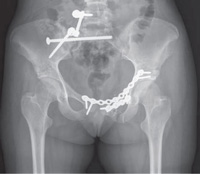

In this x-ray, an external fixator has been used to stabilize the pelvis.

Reproduced from Kurylo JC, Tornetta P: Initial management and classification of pelvic fractures. Instructional Course Lecture 61. Rosemont, IL, American Academy of Orthopaedic Surgeons, 2012, pp. 3-18.

In this x-ray, plates and screws have been used to repair a fractured pelvis.

Reproduced from Mullis BH: Techniques of anterior pelvic fixation. Instructional Course Lecture 61. Rosemont, IL, American Academy of Orthopaedic Surgeons, 2012, pp. 19-25.

External fixation. Your doctor may use external fixation to stabilize your pelvic area. In this operation, metal pins or screws are inserted into the bones through small incisions into the skin and muscle. The pins and screws project out of the skin on both sides of the pelvis where they are attached to carbon fiber bars outside the skin. The external fixator acts as a stabilizing frame to hold the broken bones in proper position.

Open reduction and internal fixation. During this operation, the displaced bone fragments are first repositioned (reduced) into their normal alignment. They are then held together with screws or metal plates attached to the outer surface of the bone.